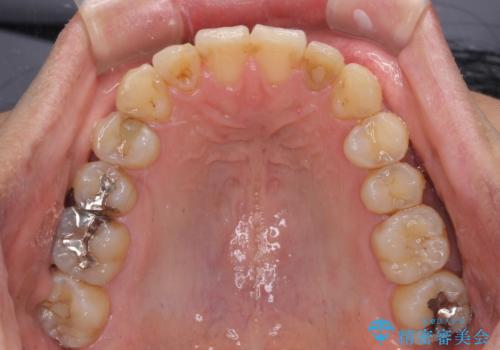

前歯のデコボコと下顎の八重歯 インビザラインによる矯正治療

- 1年4ヶ月

- 前歯のデコボコや八重歯を気にして来院された患者様です。

インビザラインを用いて、歯列を整えることとしました。